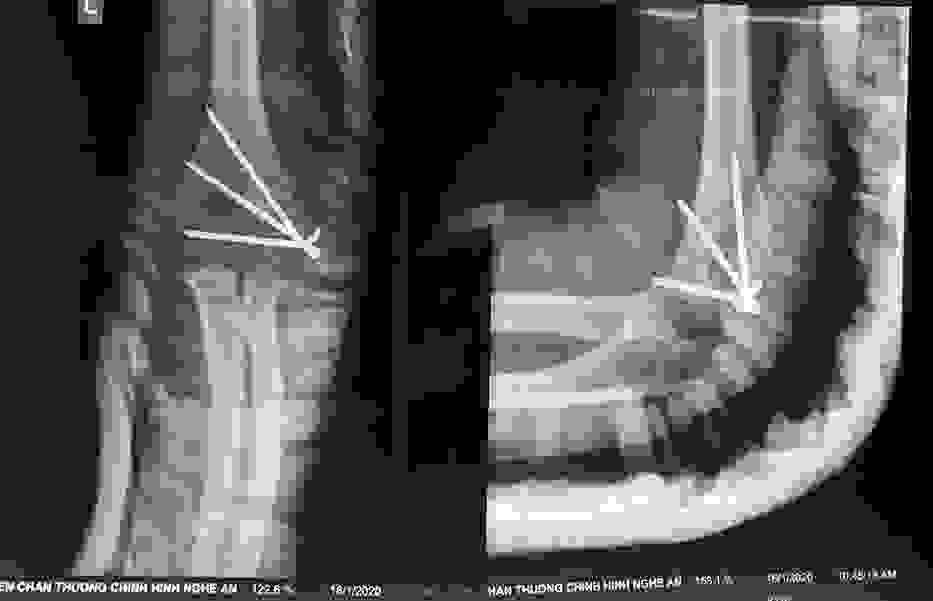

Điều trị gãy lồi cầu ngoài xương cánh tay ở trẻ em

12/03/2020 17:00

Đã xem: 5770